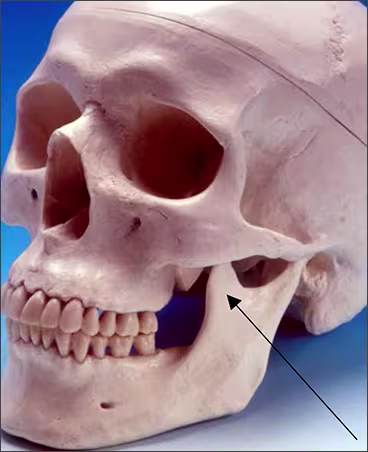

Coronoid process – The coronoid process of the mandible is the triangular bony portion of the anterosuperior aspect of the ramus (Figure 17 A). This mandibular structure can be recorded on maxillary molar periapical images as the ramus moves forward when the patient’s mouth is open. It appears as a bilateral triangular or thumb-like radiopacity on posterior maxillary images (Figures 17 B&C). The triangular portion projects forward toward the midline. The coronoid process is the only mandibular structure recorded on maxillary molar periapical images.

Figures 17 A,B,C: Coronoid Process